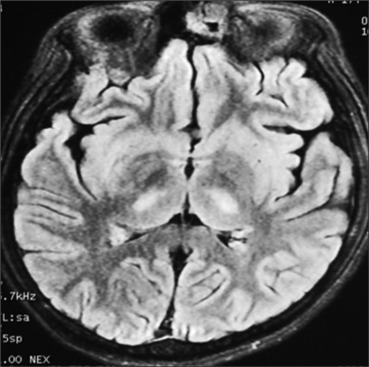

血栓性微血管病变(TMAs)是一组以微血管致病性溶血性贫血和血小板减少为特征的疾病,可导致缺血性组织损伤。我们在此,描述一个有趣的病例TMA继发于登革热与登革脑炎。与登革热相关的TMA很少被描述。入院后几小时内,基于高血浆评分,在多功能细胞分离器(Spectra Optia, Terumo BCT,美国)上进行标准体积(1.5血浆体积)治疗性血浆交换(TPE)治疗,导致溶血参数和肾损伤得到改善。这一病例突出了早期诊断和早期开始TPE的作用,是管理与登革热相关的tma的关键。

Thrombotic microangiopathies (TMAs) are a group of disorders characterized by microangiopathic hemolytic anemia and thrombocytopenia, leading to ischemic tissue injury. We, hereby, describe an interesting case of TMA secondary to dengue along with dengue encephalitis. Dengue-related TMA is rarely described. Treatment was initiated with standard-volume (1.5 plasma volume) therapeutic plasma exchange (TPE) by centrifugation method on a multifunctional cell separator (Spectra Optia, Terumo BCT, USA) within a few hours of admission based on high PLASMIC score, which led to improvement in hemolytic parameters and kidney injury. This case highlights the role of early diagnosis and early initiation of TPE is key in the management of dengue-related TMAs.